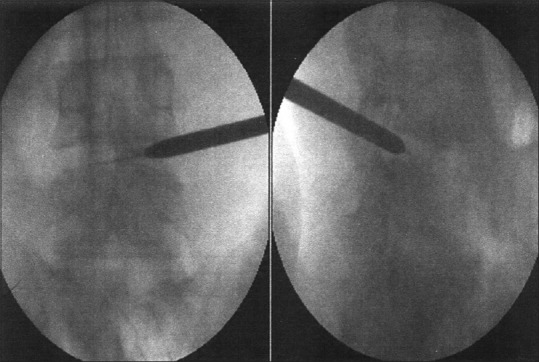

A guide wire is introduced through the needle, and the passage is dilated with the obturator that is threaded onto the guide wire till it reaches the annulus [Figure 3]. The next step was annular fenestration, in which the blunt-tapered obturator was advanced manually or with a mallet (patient is sedated before thrusting the obtuator past the annulus) [Figure 4]. A beveled working cannula is guided over the dilator to position it into the disc [Figure 5]. The next step is fragmentectomy where the decompression is done from medial to lateral aspect of the disc using rongeurs of various sizes under direct vision [Figure 6]. After decompressing the dural sac laterally to the spinous process in the AP view guided by the C-arm, the working cannula was retracted until it reached the medial pedicular line and the foramen. The decision of adequate decompression was accomplished by visual inspection of mobility of a free-floating dural sac and epidural space [Figure 7].

Figure 3.

Inserted guide wire in the disc space over which obturator is being inserted

Figure 4.

Annular fenestration being done by advancing the obturator

Figure 5.

Working sleeve inserted over obturator